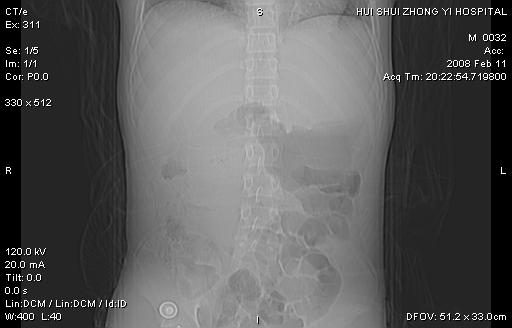

8年前曾在贵洲省人民医院b超诊断为肝内胆管结石。现腹痛剧烈,现发烧、头痛、恶心呕吐县医院b超示胆囊肿大大小159*46mm,囊内见6*5mm强回声光团,胆各总管内径56mm。提示:胆囊结石、急性胆囊炎、胆总管重度扩张。

胆囊结石.急性胆囊炎.重度胆管扩张.右侧胸腔少量积液,建议ct增强

考虑先天性胆管囊肿;胆囊增大并结石。右侧胸腔少量积液,建议ct增强。

先天性胆管囊肿,胆囊结石、胆囊增大,右侧少量胸腔积液。